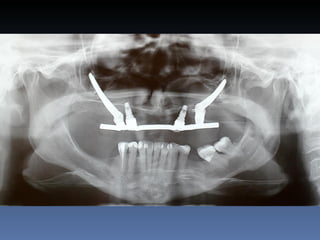

Diagnóstico: Desdentada total maxila

já reabilitada com “All-on-four” híbrido;

periimplantite dos implantes anteriores.

Plano de tratamento:         Remoção dos implantes

anteriores, instalação de dois implantes Zigomáticos

e dois implantes posteriores na tuberosidade.